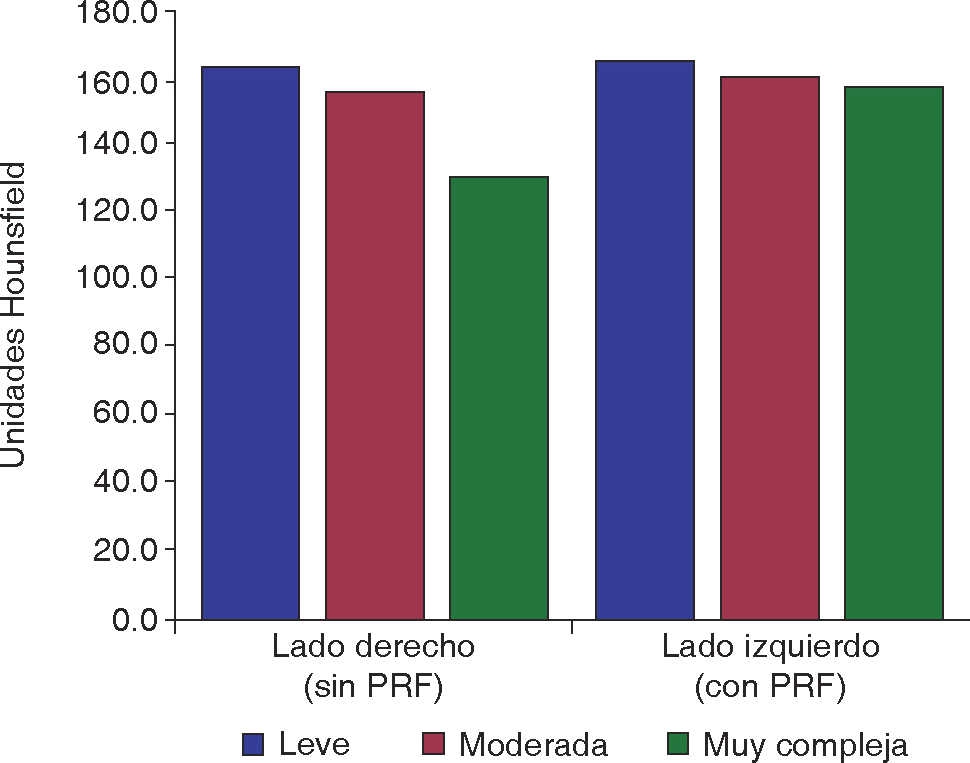

De los 30 pacientes incluidos en el estudio, 15 fueron del sexo femenino y 15 del sexo masculino. Fueron agrupados por edad, 8 pacientes de 16 a 19 años, 15 pacientes de 20 a 23 años, y 7 pacientes de 24 a 27 años (Figura 4). Se catalogaron por dificultad de extracción según la clasificación de Pederson17 en leve, moderada y muy compleja, con resultados de 7 leves, 22 moderadas y una muy compleja en el lado derecho y 8 leves, 20 moderadas y 2 muy complejas en el lado izquierdo (Figura 5).

La cicatrización del tejido óseo tuvo mejor puntuación en el lado experimental con valores de densidad de 163.9 HU comparado con el lado control de 159.3 HU (Figura 7). La prueba t de Student dio un resultado de p = 0.015. Con relación al sexo y edad no se obtuvieron diferencias (Cuadro I). De acuerdo con la propuesta de criterios y escala de puntuaciones de Pederson, con relación a la dificultad de extracción, los mejores resultados se obtuvieron para los grupos de leve complejidad de extracción (Figura 8).

Por último, la dificultad de la extracción dentaria fue calculada mediante la escala de Pederson.17 Los mejores valores medios se presentaron en el grupo experimental y en el subgrupo denominado como extracción de leve complejidad; aunque estadísticamente no indica influencia la complejidad de la cirugía con la cicatrización ósea.

El estudio demostró que la cicatrización de tejido blando y tejido óseo mejora con el uso de PRF, afirmando de esta manera su efectividad. Analizando por el grupo de edad, el de 20 a 23 años presentó mejor cicatrización de tejido óseo, comparado con el de 16 a 19 años que presentó el mejor resultado en cicatrización de tejido blando. Con relación al sexo masculino y femenino presentó mejor cicatrización el sexo masculino. Por último con respecto a la dificultad de extracción del tercer molar, no se vio influenciada la cicatrización en valores significativos, tanto en casos complejos, de mediana complejidad o en los que la cirugía se tornó rápida y fácil.